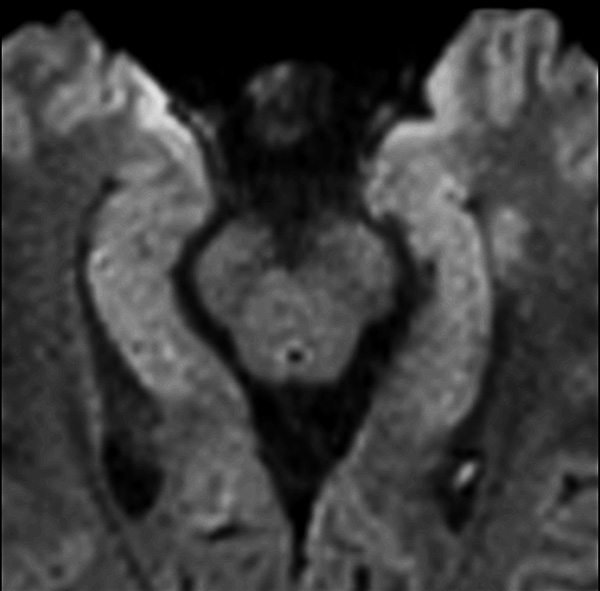

Comprehensive Brain imaging at 1.5T

Used Solution